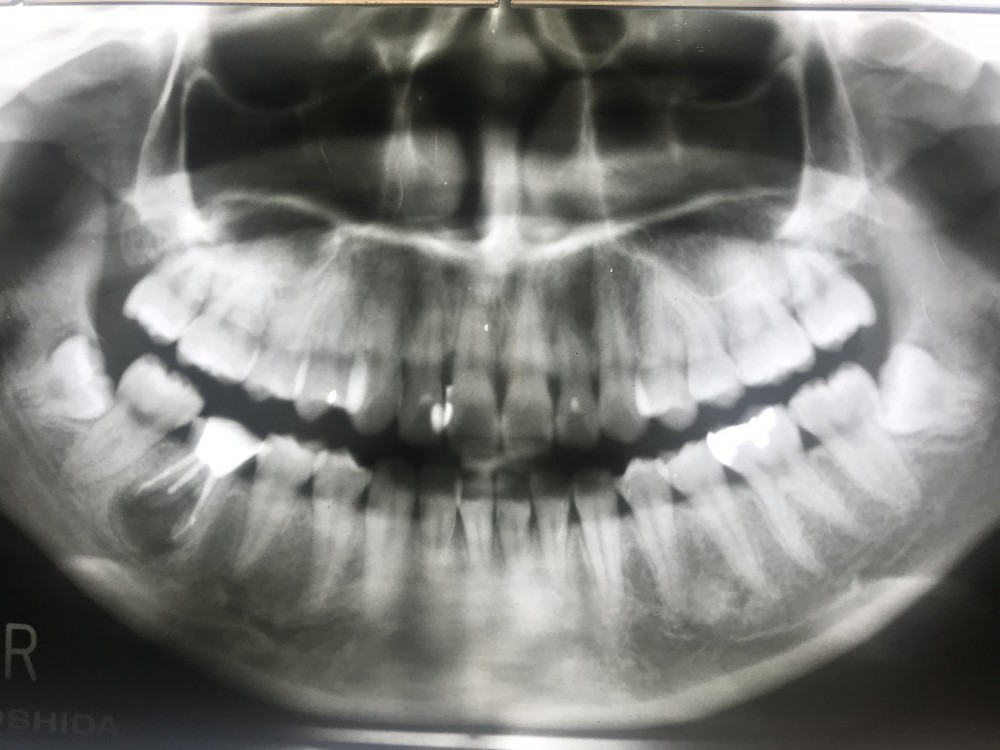

下の画像は初診時より8ヶ月後のもの。

根管充填行っています。